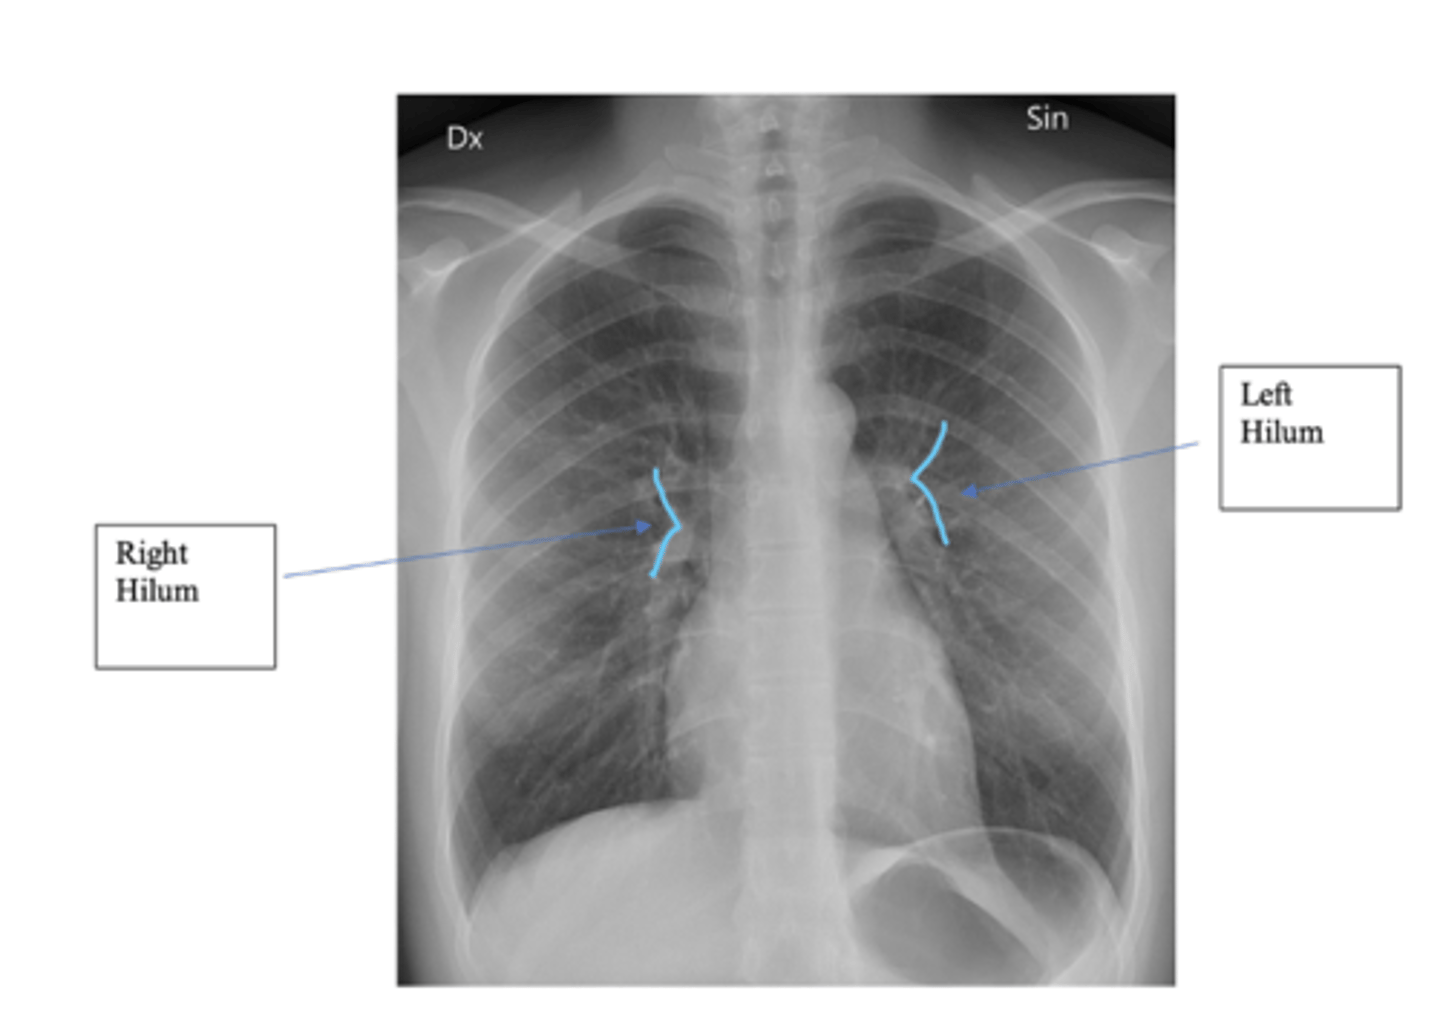

What do the Hilar structures consist of? Is the L or R positioned higher? Why is it important to ID this structure?

•The hilar consist of the main pulmonary vasculature and the major bronchi. (wedge shaped area on central portion of each lung)

•Each hilar also has a collection of lymph nodes which aren’t usually visible in healthy individuals.

•The left hilum is often positioned slightly higher than the right, but there is a wide degree of variability between individuals.

•The hilar are usually the same size, so asymmetry should raise suspicion of pathology.

<p>•The hilar consist of the main pulmonary vasculature and the major bronchi. (wedge shaped area on central portion of each lung)</p><p>•Each hilar also has a collection of lymph nodes which aren’t usually visible in healthy individuals.</p><p>•The left hilum is often positioned slightly higher than the right, but there is a wide degree of variability between individuals.</p><p>•The hilar are usually the same size, so asymmetry should raise suspicion of pathology.</p>

What is the significance of the hilar point?

⚬where the descending pulmonary artery intersects the superior pulmonary vein.

⚬When this is lost, consider the possibility of a lesion here (e.g. lung tumour or enlarged lymph nodes).

<p>⚬where the descending pulmonary artery intersects the superior pulmonary vein.</p><p>⚬When this is lost, consider the possibility of a lesion here (e.g. lung tumour or enlarged lymph nodes).</p>

What is mediastinal shift? How can you ID?

Left hilum should be higher than the right hilum. Often due to mediastinal mass

<p>Left hilum should be higher than the right hilum. Often due to mediastinal mass</p>